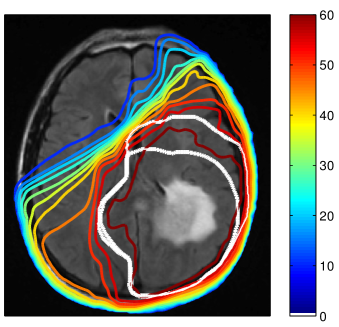

Refer to caption

Figure 3: Simulated tumor cell density based on the segmentation in figure 2 for parameters λw=4.2subscript𝜆𝑤4.2\lambda_{w}=4.2 mm and Dw/Dg=100subscript𝐷𝑤subscript𝐷𝑔100D_{w}/D_{g}=100 (a) and Dw/Dg=10subscript𝐷𝑤subscript𝐷𝑔10D_{w}/D_{g}=10 (b) . The color scale refers to the log10𝑙𝑜subscript𝑔10log_{10} cell density normalized to the carrying capacity.

In this paper, we are concerned with the spatial definition of the target volume as an isoline of the tumor cell density. In that context, the exact value of the infiltration length λwsubscript𝜆𝑤\lambda_{w} is irrelevant because it does not affect the shape of the isolines. Only the abolute values of the tumor cell density associated with the isolines are determined by λwsubscript𝜆𝑤\lambda_{w} 333The value of λwsubscript𝜆𝑤\lambda_{w} will be crucial for dose prescription considered in the accompanying paper [16].. Thus, the only relevant model parameter for this paper is the ratio Dw/Dgsubscript𝐷𝑤subscript𝐷𝑔D_{w}/D_{g}, which determines the shape of the isolines of the cell density together with the brain segmentation. The literature consistently suggests that tumor cells infiltrate gray matter much less than white matter444This holds for the most common case of astrocytomas, not necessarily for oligodentrogliomas (see [12] for a review of glioma growth patterns). This suggests a large value for Dw/Dg1much-greater-thansubscript𝐷𝑤subscript𝐷𝑔1D_{w}/D_{g}\gg 1. Most illustrations in this paper were obtained for Dw/Dg=100subscript𝐷𝑤subscript𝐷𝑔100D_{w}/D_{g}=100. The most appropriate value is however uncertain and we discuss the impact of uncertainties in Dw/Dgsubscript𝐷𝑤subscript𝐷𝑔D_{w}/D_{g} in section 3.5.

Using the tumor growth model, the target volume can be defined as an isoline of the tumor cell density. This is illustrated here for the tumor cell density shown in figure 3a obtained for the parameter value Dw/Dg=100subscript𝐷𝑤subscript𝐷𝑔100D_{w}/D_{g}=100. The red and the orange contours in figure 4 show the CTV and the boost volume derived from the tumor growth model, respectively. In this example, the target defining isolines are chosen such that the total enclosed volume is equal to the manually delineated target. In the following two subsections, we discuss the differences between manual and model-derived target volumes in detail.

In addition to the segmentation, the ratio of white and gray matter diffusion coefficient Dw/Dgsubscript𝐷𝑤subscript𝐷𝑔D_{w}/D_{g} influences the shape of the isolines of the tumor cell density. For Dg=0subscript𝐷𝑔0D_{g}=0, gray matter represents a hard boundary and tumor cells only spread in white matter. For Dw/Dg=1subscript𝐷𝑤subscript𝐷𝑔1D_{w}/D_{g}=1, tumor cells spread equally in white and gray matter and the shape of the target is solely influenced by anatomical constraints. In figure 3 the simulated tumor cell density is compared for Dw/Dg=10subscript𝐷𝑤subscript𝐷𝑔10D_{w}/D_{g}=10 and Dw/Dg=100subscript𝐷𝑤subscript𝐷𝑔100D_{w}/D_{g}=100. For smaller Dw/Dgsubscript𝐷𝑤subscript𝐷𝑔D_{w}/D_{g}, the cell density is more washed out (figure 3b) compared to a larger Dw/Dgsubscript𝐷𝑤subscript𝐷𝑔D_{w}/D_{g} where the tumor cell density follows more closely the white matter structure (figure 3a). It has been discussed above that the cortical gray matter has a thickness of only a few millimeters. As a consequence, varying Dw/Dgsubscript𝐷𝑤subscript𝐷𝑔D_{w}/D_{g} has little impact on the global shape of the target volume. The most significant changes for this patient are around the lateral sulcus.